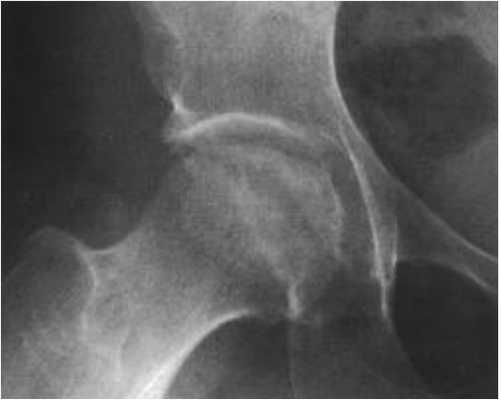

Снимок 2. Пациент обратился к врачу по поводу боли в правом паху и правом бедре, возникающей только при ходьбе или вставании со стула.

Коксартроз 2-й стадии. Фотография из архива доктора Евдокименко

В результате пациента 2 года (!) лечили от несуществующего остеохондроза. Но поскольку пациенту становилось только хуже, его, наконец, отправили на обследование. И провели, помимо прочего, рентген тазобедренных суставов. После получения рентгеновских снимков врачи наконец смогли (спустя 2 года) поставить правильный диагноз: «коксартроз».

Вот что мы видим на снимке пациента:

- головка бедренной кости «подтянулась» к вертлужной впадине, расстояние между костями совсем небольшое (уменьшение размеров суставной щели). Это говорит о том, что суставной хрящ, покрывающий сочленяющиеся части костей, стал гораздо тоньше (как вы помните, на рентгене сам хрящ не виден);

- оставшись без «хрящевого амортизатора», головка бедренной кости стала деформироваться, частично расплющиваться. Она теперь не такая идеально-круглая, как должна быть.

Такие рентгенологические изменения соответствуют коксартрозу второй стадии.